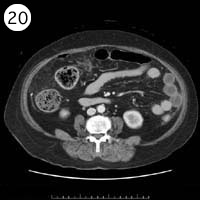

57歳 女性

単純CT

造影CT